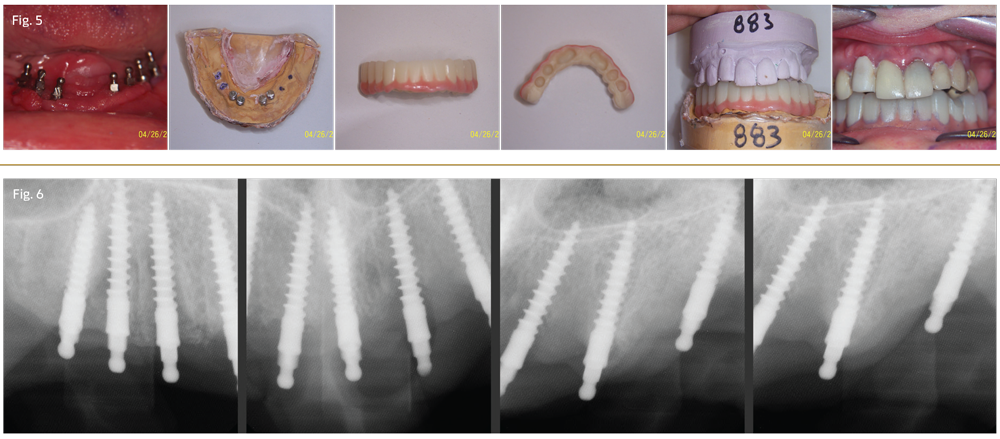

Figure 1

Visit #1: We gathered all diagnostic data—full-mouth radiographs (Fig. 1), preop photos (Fig. 2), CBCT scan (Fig. 3) and study model impressions. The patient was mildly sedated—30 milligrams of hydroxyzine slurry swallowed and 0.125mg triazolam crushed sublingually—and monitored with pulse oximeter throughout the treatment phase of the appointment.